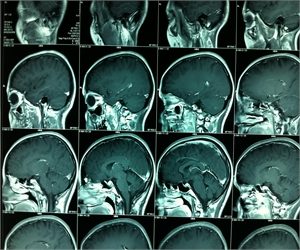

Prolaktinoma – Hipofiz Tümörü

PRL seviyelerine göre olası sebepler hakkında fikir yürütülebilinir (Tablo 3). Tümör boyutu ve PRL seviyeleri iyi korelasyon gösterir ve bir makroadenomda PRL seviyeleri genellikle 200 ng/ml ve üzeridir. 500 ng/ml üzeri genellikle makroprolaktinoma için diagnostiktir. 250 ng/ml üzerinde prolaktin seviyesi genellikle prolaktinoma varlığını göstersede özellikle risperidon ve metoklopromid kullananlarda adenom olmasa da prolaktin 200 üzerine çıkabilir. Eğer hipofiz MR’da tespit edilen makroadenom ile PRL seviyeleri arasında korelasyon yok ise adenom nonfonksiyonel bir adenom olabilir ve bu durumda PRL yüksekliği sap basısına bağlanır. Histolojik olarak doğrulanmış non fonksiyone pitutier makroadenomlu 226 hasta üzerinde yapılan bir çalışmada 94ng/ml üzerinde prolaktin düzeyi prolaktinoma ile non fonksiyone adenomu güvenilir bir şekilde ayırt etmiştir. Bir diğer olasılık ise “hook effect -kanca etki” dir. Laboratuvar yöntemiyle ilgili olan bu sorunda PRL seviyeleri yalancı olarak düşük çıkmaktadır. Bu durumda serumun 1:100 oranında sulandırılarak yeniden çalışılması uygun olur.